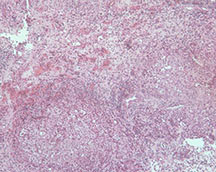

Microscopic Pathology

- Langerhans cell is diagnostic and clonal proliferation

- Nuclei show prominent nuclear groove (coffee-bean)

- Also composed of eosinophils and other inflammatory cells (non diagnostic component)

- Ratio of inflammatory cells to Langerhans cells varies

- Mitotic activity low

- Eosinophils dominate some areas forming diffuse sheets, excluding Langerhans cells